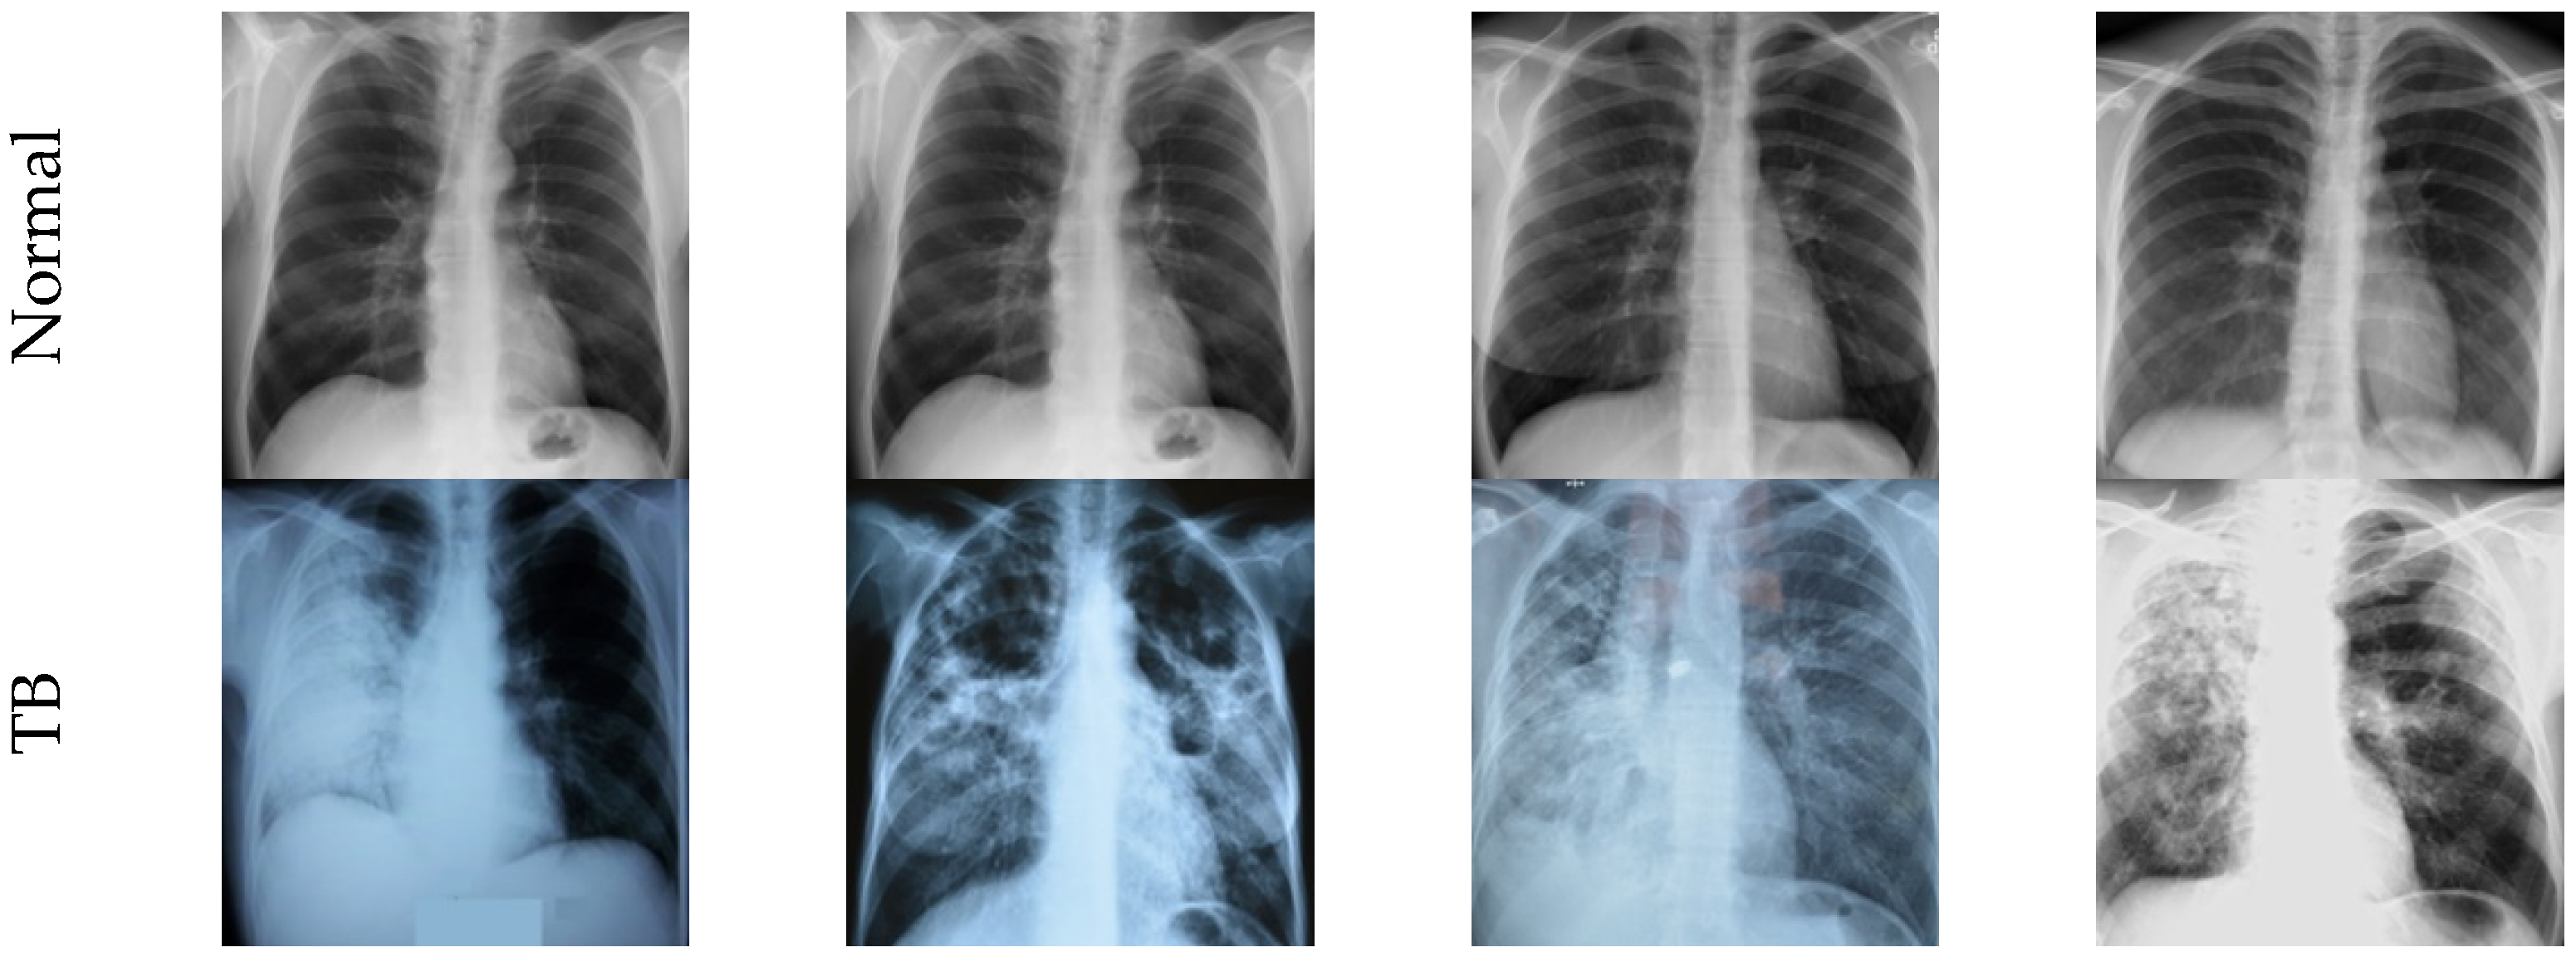

3.1. Image Dataset